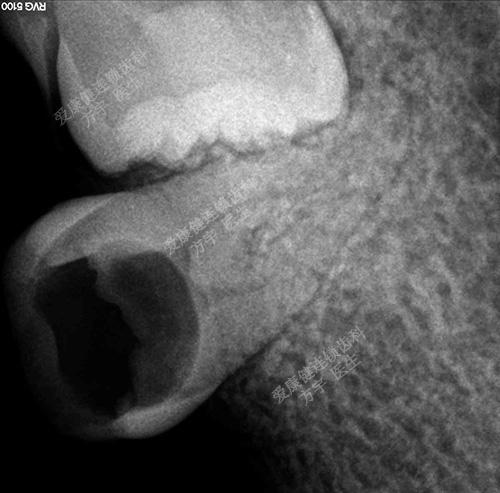

术前